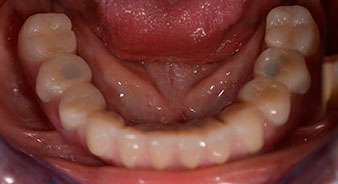

Para la planificación y la minimización del riesgo, se realizó una tomografía volumétrica tridimensional (TVD, Planmeca) que mostró que la calidad y la cantidad del tejido óseo era suficiente para la intervención quirúrgica y el tratamiento inmediato con el método Fast & Fixed. Siguiendo el protocolo de este método, se insertaron los implantes en la región de las piezas 35, 32, 42 y 45. Debido a la inclinación de hasta 45 grados de los implantes distales, el perfil de emergencia se desplazó hacia posterior y se generó un mayor polígono de soporte (fig. 3).